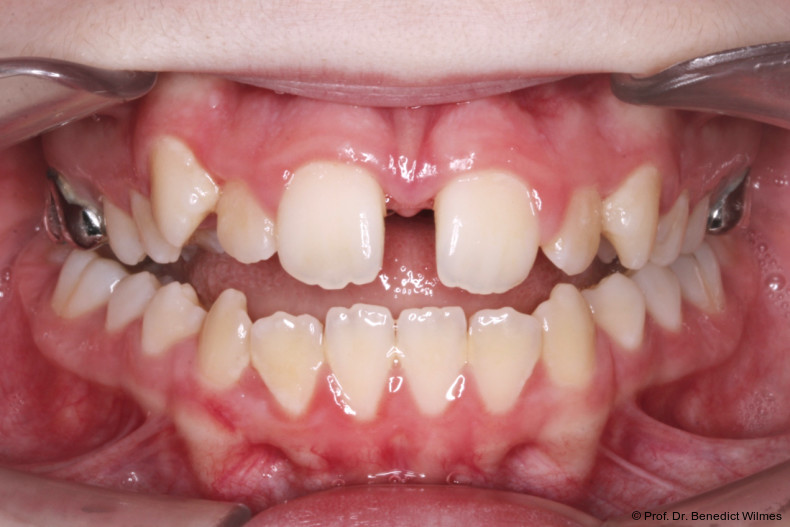

Eine 13-jährige Patientin stellte sich mit beidseitigem Kreuzbiss, einem anterioren offenen Biss und einer Angle Klasse II vor. Das viszerale Schluckmuster wurde mittels logopädischer Maßnahmen umgestellt, der offene Biss persistierte jedoch (Abb. 3a–l).